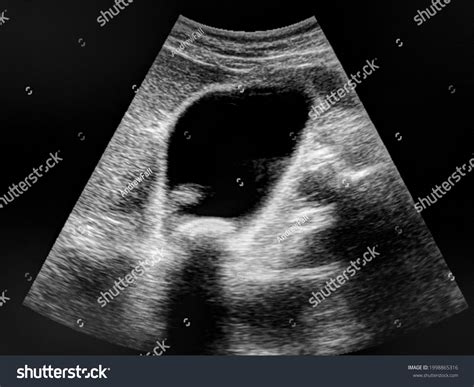

Ultrasound is frequently the first-line imaging modality for patients presenting with biliary symptoms. It is non-invasive, widely available, and does not involve ionizing radiation. When a sonographer assesses the biliary tree, they are specifically looking for evidence of biliary obstruction, which is often the indirect sign of a stone trapped in the duct.

The diagnostic power of Choledocholithiasis On Ultrasound primarily relies on identifying:

• Dilation of the Common Bile Duct (CBD): A duct measuring over 6–7 mm is often considered dilated, suggesting a potential obstruction.

• Direct Visualization of Stones: While challenging due to bowel gas, high-frequency transducers can sometimes visualize echogenic foci with acoustic shadowing within the duct.